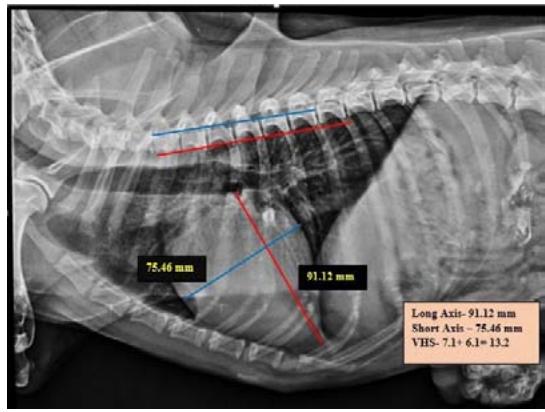

Tracheal Diameter: Tracheal Inlet (TD: TI) ratio was calculated by recording the diameter of the trachea at the level of the thoracic inlet and the inner diameter of the thoracic inlet (Fig 1). Cardiothoracic ratios (CTR) were calculated by dividing the largest width of the thorax by chest depth on radiographs (Fig 3). On a dorsoventral/ventrodorsal radiograph, the width of the thorax was measured as the distance between the medial borders of the eight ribs (Fig 4). The depth was assessed on the right lateral radiographic view from the dorsal margin of the xiphoid process to the ventral margin of the vertebral body, with the electronic calipers aligned perpendicular to the vertebral column. The Vertebral heart score was calculated according to Buchanan and Bucheler, 1995 (Fig 2).

From measurements of Vertebral Heart Score in both right lateral and left lateral thoracic radiographs, 33.33 percent of group I animals and 25 percent of group II animals were diagnosed as suffering from cardiomegaly. There was no significant difference between the groups. A VHS over 10.7 on the lateral radiograph was a moderately accurate sign of cardiac disease, as opined by Lamb et al. (2000). The highest vertebral heart score in the dogs might be due to the onset of mitral valve regurgitation following congestive heart failure, as documented by Lord (2010). The pulmonary metastases of malignancy might be lead to epicardial, myocardial and, endocardial involvement and further pathophysiological changes such as pericardial effusion, filling impairment, myocardial dysfunction, etc., as documented by Bussani et al. (2007).

Fig. 2: Skiagram showing measurement of vertebral heart score from the right lateral view